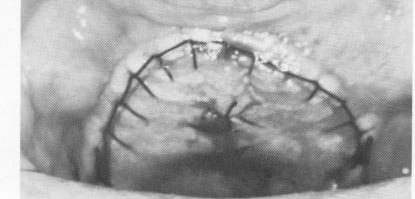

Fig. 12-111. A, The incision was made. B, The palatal tissue was retracted. C, An acrylic tray was cold cured. D, A rubber base impression of the hard palate was taken inside the acrylic tray. E, The tissues were sutured together.